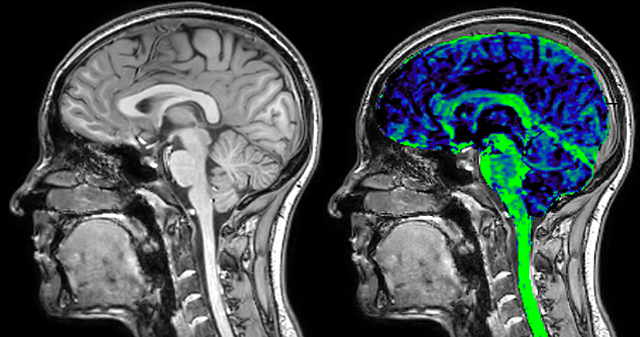

Dr. Rauscher says, “With better gradients we can use a shorter echo spacing on the spin echo, so we get better sampling of the rapidly decaying myelin signal, which typically has T2 of around 10-20 milliseconds at 3 Tesla. If we can reduce echo spacing from about 8 to 5-6 milliseconds, we get a much better sampling of the short decay component and increase our SNR, which is a big advantage. The same is true for multi-echo gradient echo which we use for susceptibility mapping and for mapping venous vessels in MS.”

For instance, we can get the combined information from looking at advanced diffusion, multi-shell diffusion combined with myelin water, and then also add quantitative susceptibility mapping and get a better idea of tissue micro structure effects from all three combined. On the old scanner we only had time to run maybe one or two of these sequences in addition to the conventional scans,” says Dr. Rauscher.

He says the accelerated scanning is achieved via the use of Compressed SENSE and MultiBand SENSE. “We can use Compressed SENSE acceleration factors of about 10 on a 3D FLAIR for instance, which is quite remarkable compared with what we saw with the Achieva. With 3D FLAIR, we can push the spatial resolution to 0.3 cubic mm and it works. Previously, our 3D FLAIR scans lasted about 8 minutes, but now with Elition they are five minutes. The SNR is also visibly better. Our SWI and QSM scans look fantastic. Also, since a lot of neuroimaging is EPI based, using the MultiBand SENSE technique can increase temporal resolution and make it possible to run complicated DTI scans relatively quickly.”

QSM based on a Compressed SENSE multi-echo SWI.